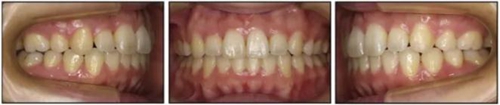

五、治療結(jié)果

治療后數(shù)據(jù)提示治療目標(biāo)達(dá)成。面相結(jié)果提示微笑及側(cè)貌得到改善(圖6)。達(dá)到了安氏I類(lèi)尖牙關(guān)系和安氏II類(lèi)磨牙關(guān)系,形成尖牙保護(hù)合。牙齒中線無(wú)偏斜,達(dá)到理想的覆合覆蓋,Spee曲線得到整平。